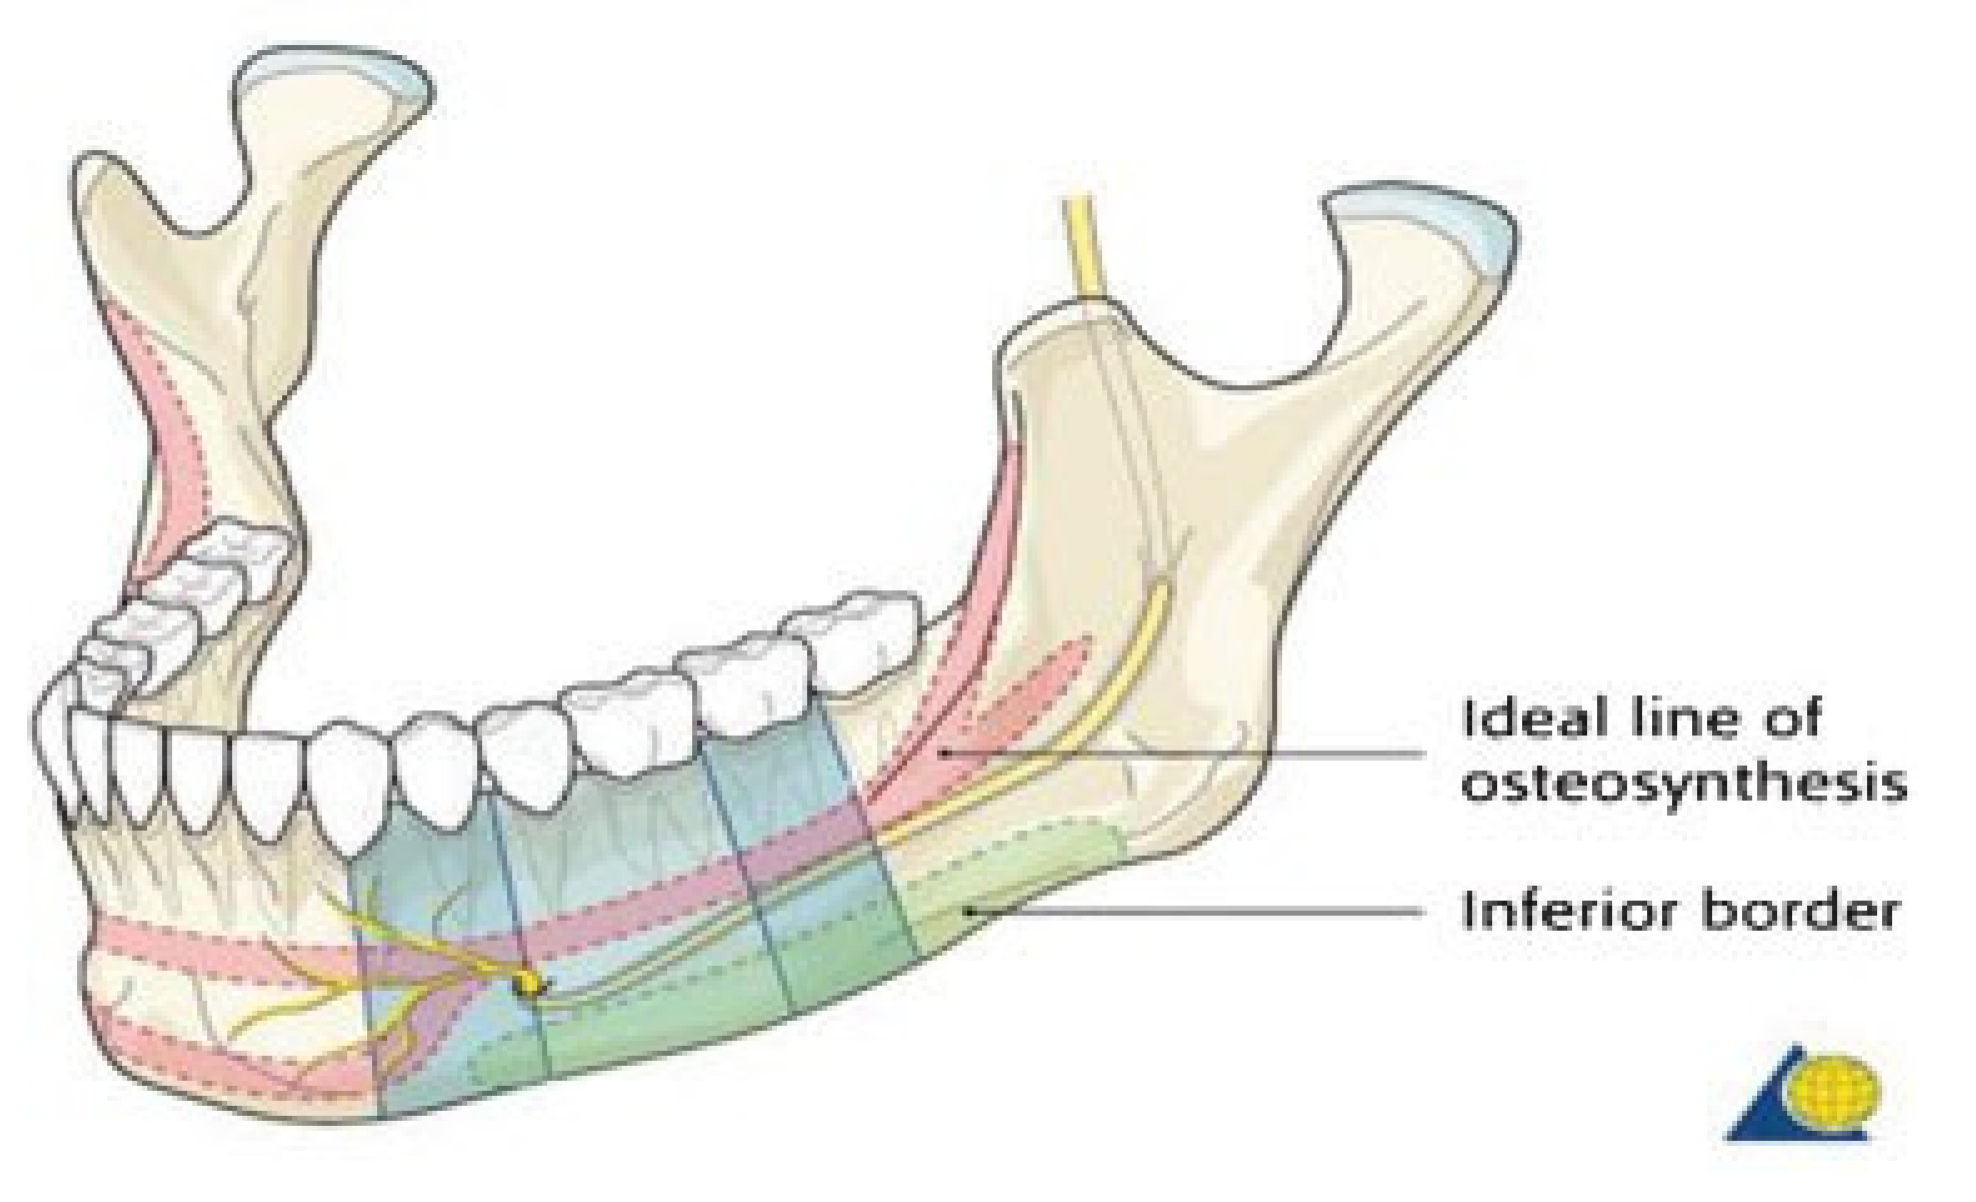

Champy and colleagues expressed that osteosynthesis will be more effective with miniplates inserted along the line called the “ideal line of osteosynthesis,” thereby counteracting the distraction forces that occur along the fracture line during mandibular function (

Figure 1). In the mandibular angle region, this line indicates that a plate might be placed either along or just below the external oblique line of the mandible [

There are controversies in the number of miniplates used in angle fixation. Champy and colleagues showed that using one miniplate along the external oblique ridge is sufficient [